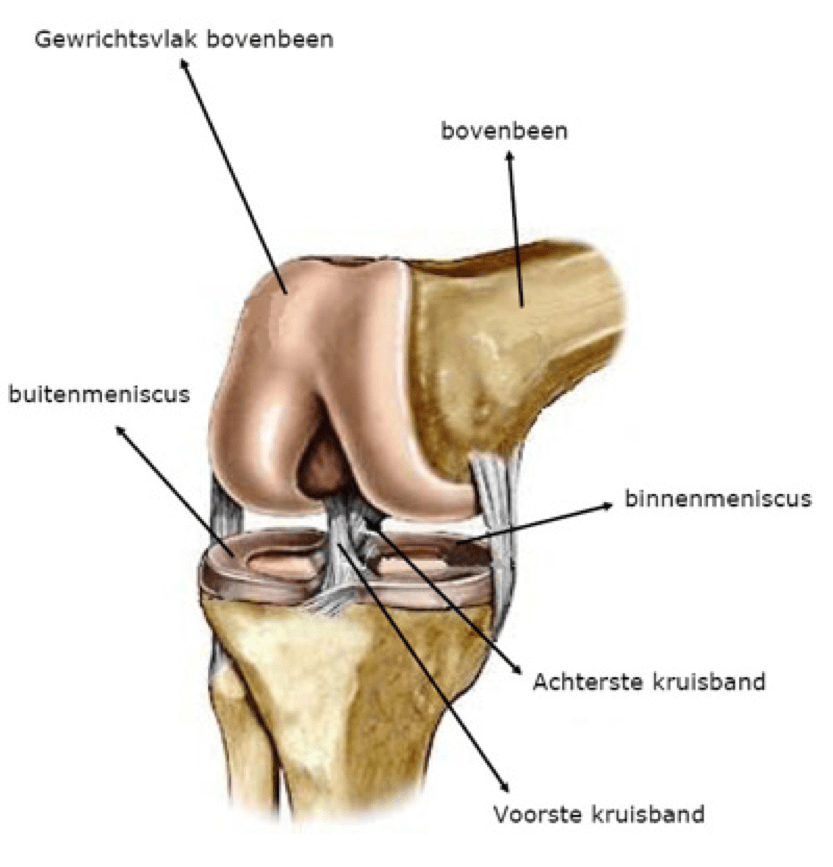

Om u te laten begrijpen wat een TKP is, willen we uitleggen hoe de anatomie van een gezond kniegewricht eruitziet.

Het kniegewricht wordt gevormd tussen het boven- of dijbeen (Lat. femur) en het scheenbeen (Lat. tibia). Zowel het bovenbeenuiteinde als het draagvlak van het onderbeen (tibia plateau) zijn bekleed met kraakbeen. Daarnaast maakt ook de knieschijf (Lat. patella) deel uit van het kniegewricht en is achteraan met kraakbeen bekleed. De knieschijf vormt het centrum van het strekapparaat van de knie en de voorzijde van het scharniergewricht. Het kniegewricht heeft drie compartimenten:

Het gewricht wordt verder gestabiliseerd door meerdere ligamenten (gewrichtsbanden) en beide menisci die ook als schokdemper werken in een natuurlijke, gezonde knie. De dijspieren geven verdere stabiliteit en kracht rond de knie. De mobiliteit van een gezonde knie bedraagt +/- 130° in diepe buiging (flexie) en bereikt een volledige strekking (extensie). Enige rotatiebeweging is in beperkte mate aanwezig.